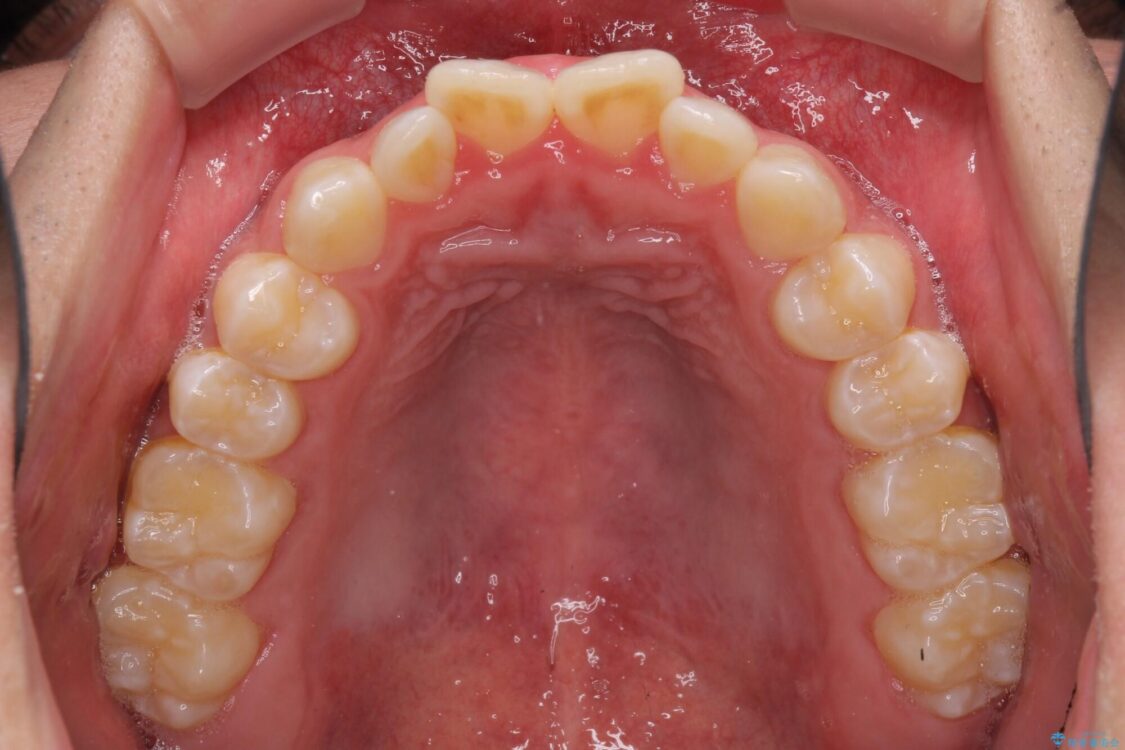

治療前

• 口元の突出感を改善 受け口傾向の咬み合わせの抜歯矯正 治療前画像

受け口傾向の咬み合わせと口元の突出感を気にして来院された患者様です。

受け口傾向特有の狭い上顎歯列であったため、歯列の拡大を補助装置で行い、下顎歯列全体を後方に移動させることとしました。